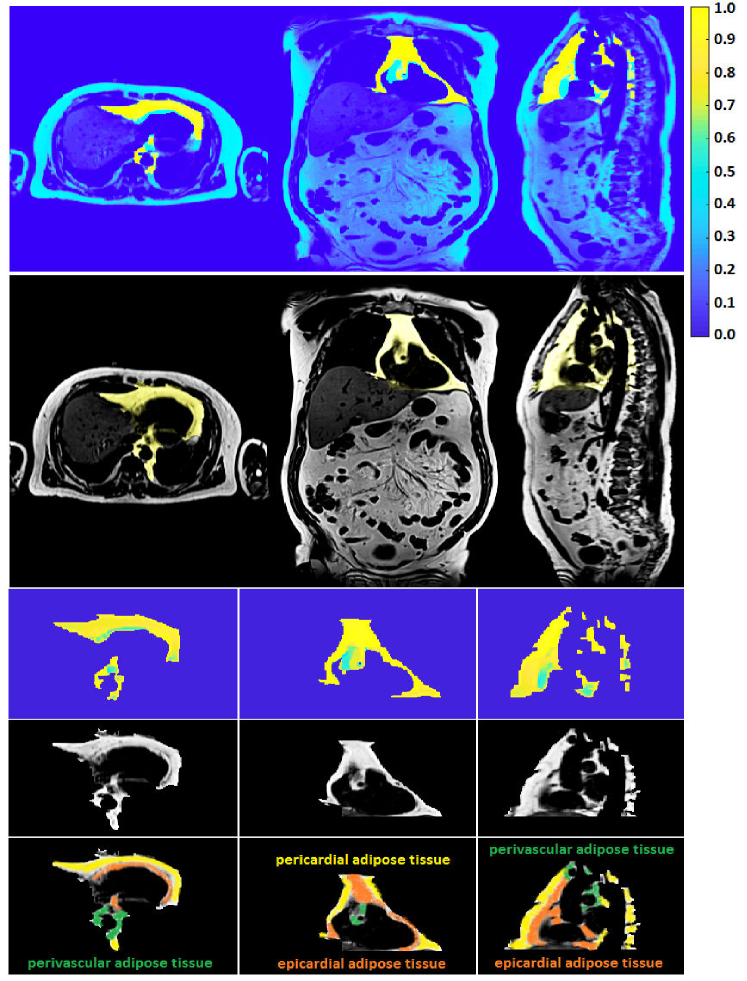

The classification priors of the samples could be estimated by any method such as the multiatlas registration or the hierarchical random forest classifier proposed in [Fallah 2018a, Fallah 2018b, Fallah 2019b, Fallah 2019a]. This happened when the classification probabilities estimated by those methods were not accurate enough to be considered as final classification probabilities (posteriors) rather as initial classification probabilities (priors). For example, the classification probabilities estimated by the proposed forest could not differentiate different kinds of cardiac adipose tissues on fat-water MR images. They could only differentiate the overall adipose tissues from nonadipose tissues. This was due to lack of spatial information in the forest, similar contrasts and features of the cardiac adipose tissues, and weak boundaries between them. The cardiac adipose tissues were spatially close to each other and separated only through thin septa which were hardly detectable under spatial resolution of standard clinical scanners at 3 T. Figure 1 shows voxelwise classification probabilities estimated by the proposed forest for the cardiac adipose tissues and the resulting segmentations on various slices of a fat image. Figure 2 shows overall segmentations of the cardiac adipose tissues based on the voxelwise classification probabilities estimated by the proposed forest on some axial slices of a fat image. Despite inaccuracies of the priors, they, features, and the spatial (neighborhood) relationships of the samples could pave the way for another classifier such as the neighborhood graph to classify the samples more accurately. For example, the priors could approximately localize an addressed object in an image and thereby speed up or reduce the complexity of its accurate segmentation. The more accurate classification probabilities were called the posteriors. Accordingly, the neighborhood graph was supposed to estimate the classification posteriors of every sample (vertex) with regard to its features, its priors, and its spatial (neighborhood) relationships with other samples of the same resolution .

The graphs proposed in section 3 and section 4 tried to implicitly or explicitly detect boundaries between different classes (e.g. objects) in spatial domain (e.g. image). The implicit boundary detection used the Tukey’s function of the features differences of the connected samples and the explicit boundary detection applied a 3D Sobel operator to each intensity channel of the samples. Both of these techniques could enhance the accuracies of a classification in spatial domain. However, their performance was limited when the features of different classes were similar or the boundaries were too weak to be detected. An example of these cases was segmentation of cardiac adipose tissues on fat-water MR images. As shown in Figure 1 and Figure 2 the random forest classifier proposed in [Fallah 2018a, Fallah 2018b, Fallah 2019b, Fallah 2019a] could only detect the overall adipose tissues but could not differentiate different kinds of it. The neighborhood graph proposed in section 3 or section 4 took the priors, the features, and the classification reliabilities of the samples and applied an implicit or explicit boundary detection. This could enhance the accuracy of the segmentation of the cardiac adipose tissues on fat-water MR images but the performance was still unsatisfactory. Figure 7 shows the voxelwise classification posteriors estimated for these adipose tissues by the implicit and/or explicit boundary detection on two axial slices of a fat image. To tackle features similarities and undetectable boundaries between different classes in spatial domain, we further extended the spatial feature-based subgraph by guiding the classification through additional information. These information got encoded into a diffusion-based susceptible-infected-recovered (SIR) model proposed in [Bampis 2017].